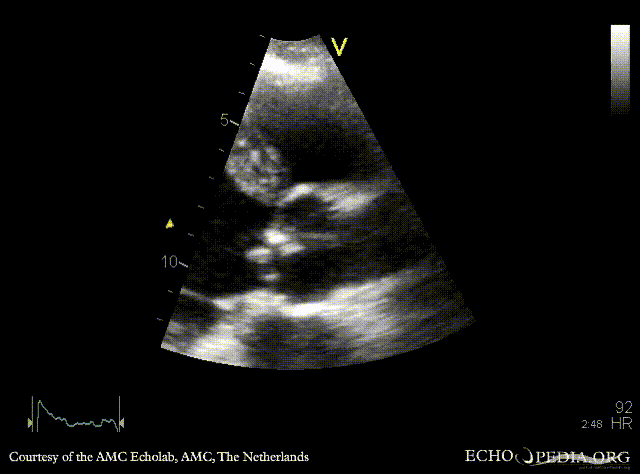

PLAX: vegetations on aortic valve PSAX: thickend bicuspid aortic valve